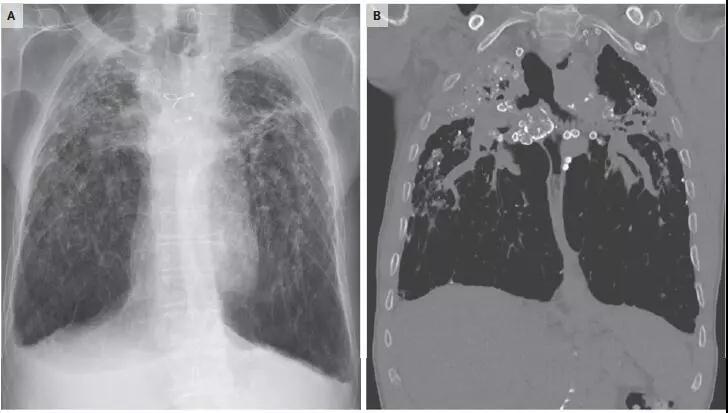

【職業(yè)病】矽肺的種類及傷殘等級

接觸哪些危害因素可引起職業(yè)病過敏性肺炎?